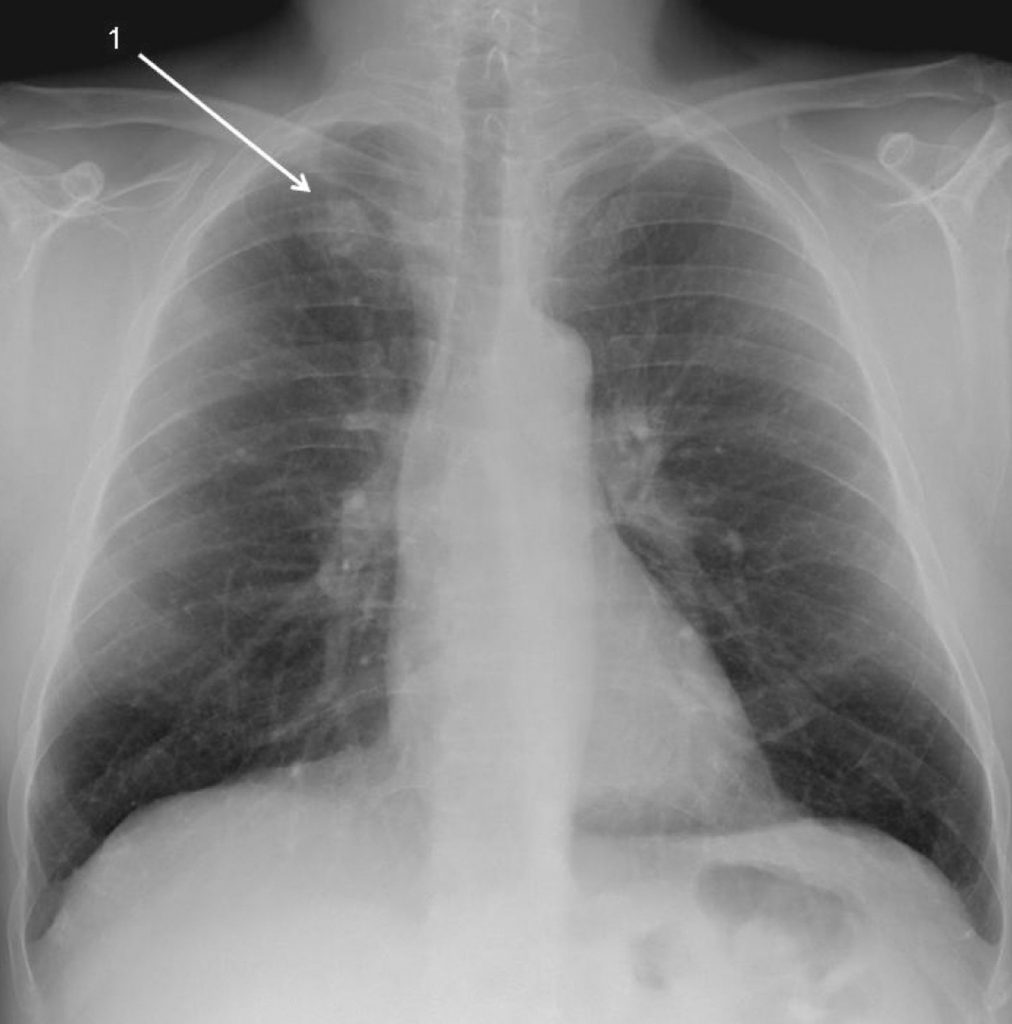

Fig. 101.1. Radiographie de face. Macronodule de l’apex pulmonaire droit (1).

Il s’agissait d’un adénocarcinome (flèche).

Source : CERF, CNEBMN, 2022.